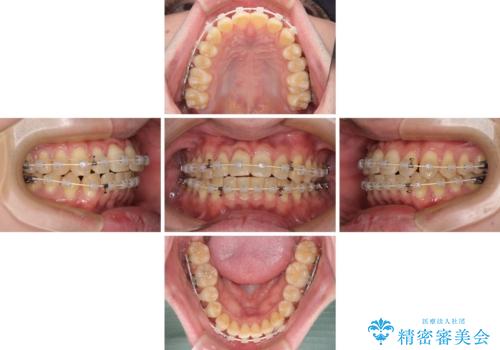

【モニター】前歯のデコボコとクロスバイト ワイヤー矯正で短期間に仕上げる

- 前歯のデコボコとクロスバイトを気にして来院された患者様です。

インビザラインでもワイヤー装置でも矯正治療は可能でしたが、煩わしい自己管理なしに短期間で治療を行いたいとのことで、目立たないワイヤー装置にて治療を行うこととしました。